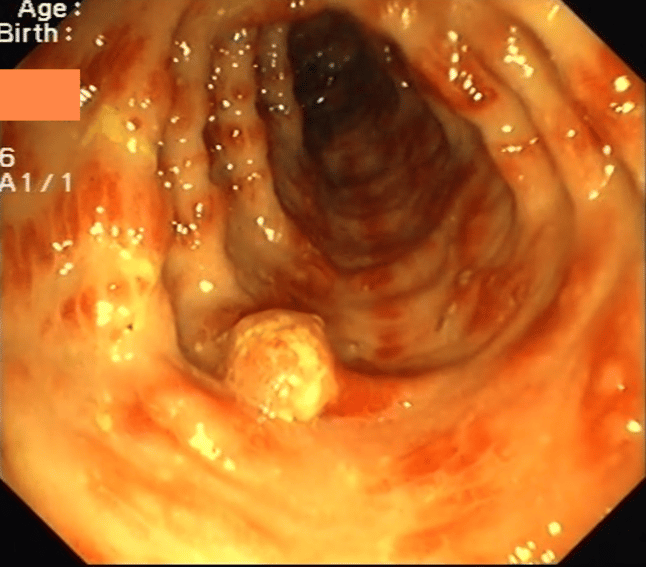

Colonoscopy showed multiple reddish, edematous mucosal streaks and polyps and pseudopolyps ranging from 5 to about 20 mm. On EGD the stomach was characterized by enlarged mucosal folds, pseudoplyps and duodenal mucosal atrophy. Histology showed the above findings (see figure 2).

CCS is a non-hereditary syndrome of unknown etiology characterized by diffuse gastrointestinal GI pseudo-polyposis, alopecia, hyperpigmentation, dystrophic changes in finger and toe nails